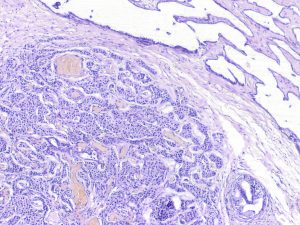

Rete Testis-Associated Nodular Steroid Cell Nests (RTANSCN) – unencapsulated nodules measuring less than 3 mm, located in rete testis. RTANSCN are composed of eosinophilic cells with round nuclei and variable prominent nucleoli arranged in nests and trabeculae with sticking sinusoidal vasculature and retraction artefact. Intracytoplasmatic Reinke crystals or lipochrome pigment are not present.

RTANSCN are usually incidental finding in patients with negative anamnesis for endocrine disorder. They are hypothesised to be the origin of the adrenogenital syndrome “tumors.”